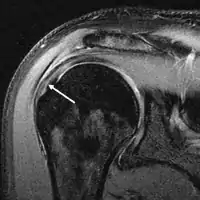

МРТ

Магнитно-резонансная томография (МРТ) и ультразвук[39] сравнимы по эффективности и полезны в диагностике, хотя оба имеют ложноположительный уровень 15–20%.[40] МРТ может надёжно обнаружить большинство разрывов на всю толщину, хотя очень маленькие точечные разрывы можно не заметить. В таких ситуациях МРТ в сочетании с инъекцией контрастного вещества, МР-артрограмма может помочь подтвердить диагноз. Следует понимать, что обычная МРТ не может полностью исключить небольшой разрыв (ложноотрицательный результат), в то время как разрывы частичной толщины не могут быть обнаружены с такой надежностью.[41] Хотя МРТ чувствительна к выявлению дегенерации сухожилия (тендинопатии), она не может надежно отличить дегенеративное сухожилие от частично разорванного сухожилия. Опять же, магнитно-резонансная артрография может улучшить дифференциацию.[41] Её общая чувствительность - 91% (т.е. 9% ложноотрицательных результатов), таким образом магнитно-резонансная артрография является надёжной при обнаружении разрывов частичной толщины вращающей манжеты манжеты.[41] Однако его обычное использование не рекомендуется, поскольку оно связано с введением в сустав иглы с потенциальным риском заражения. Следовательно, тест предназначен для случаев, когда диагноз остается неясным.